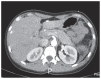

Postoperative abdominal computed tomography image showing moderate oedema of the head of the pancreas and a small fluid collection near the tail of the pancreas.